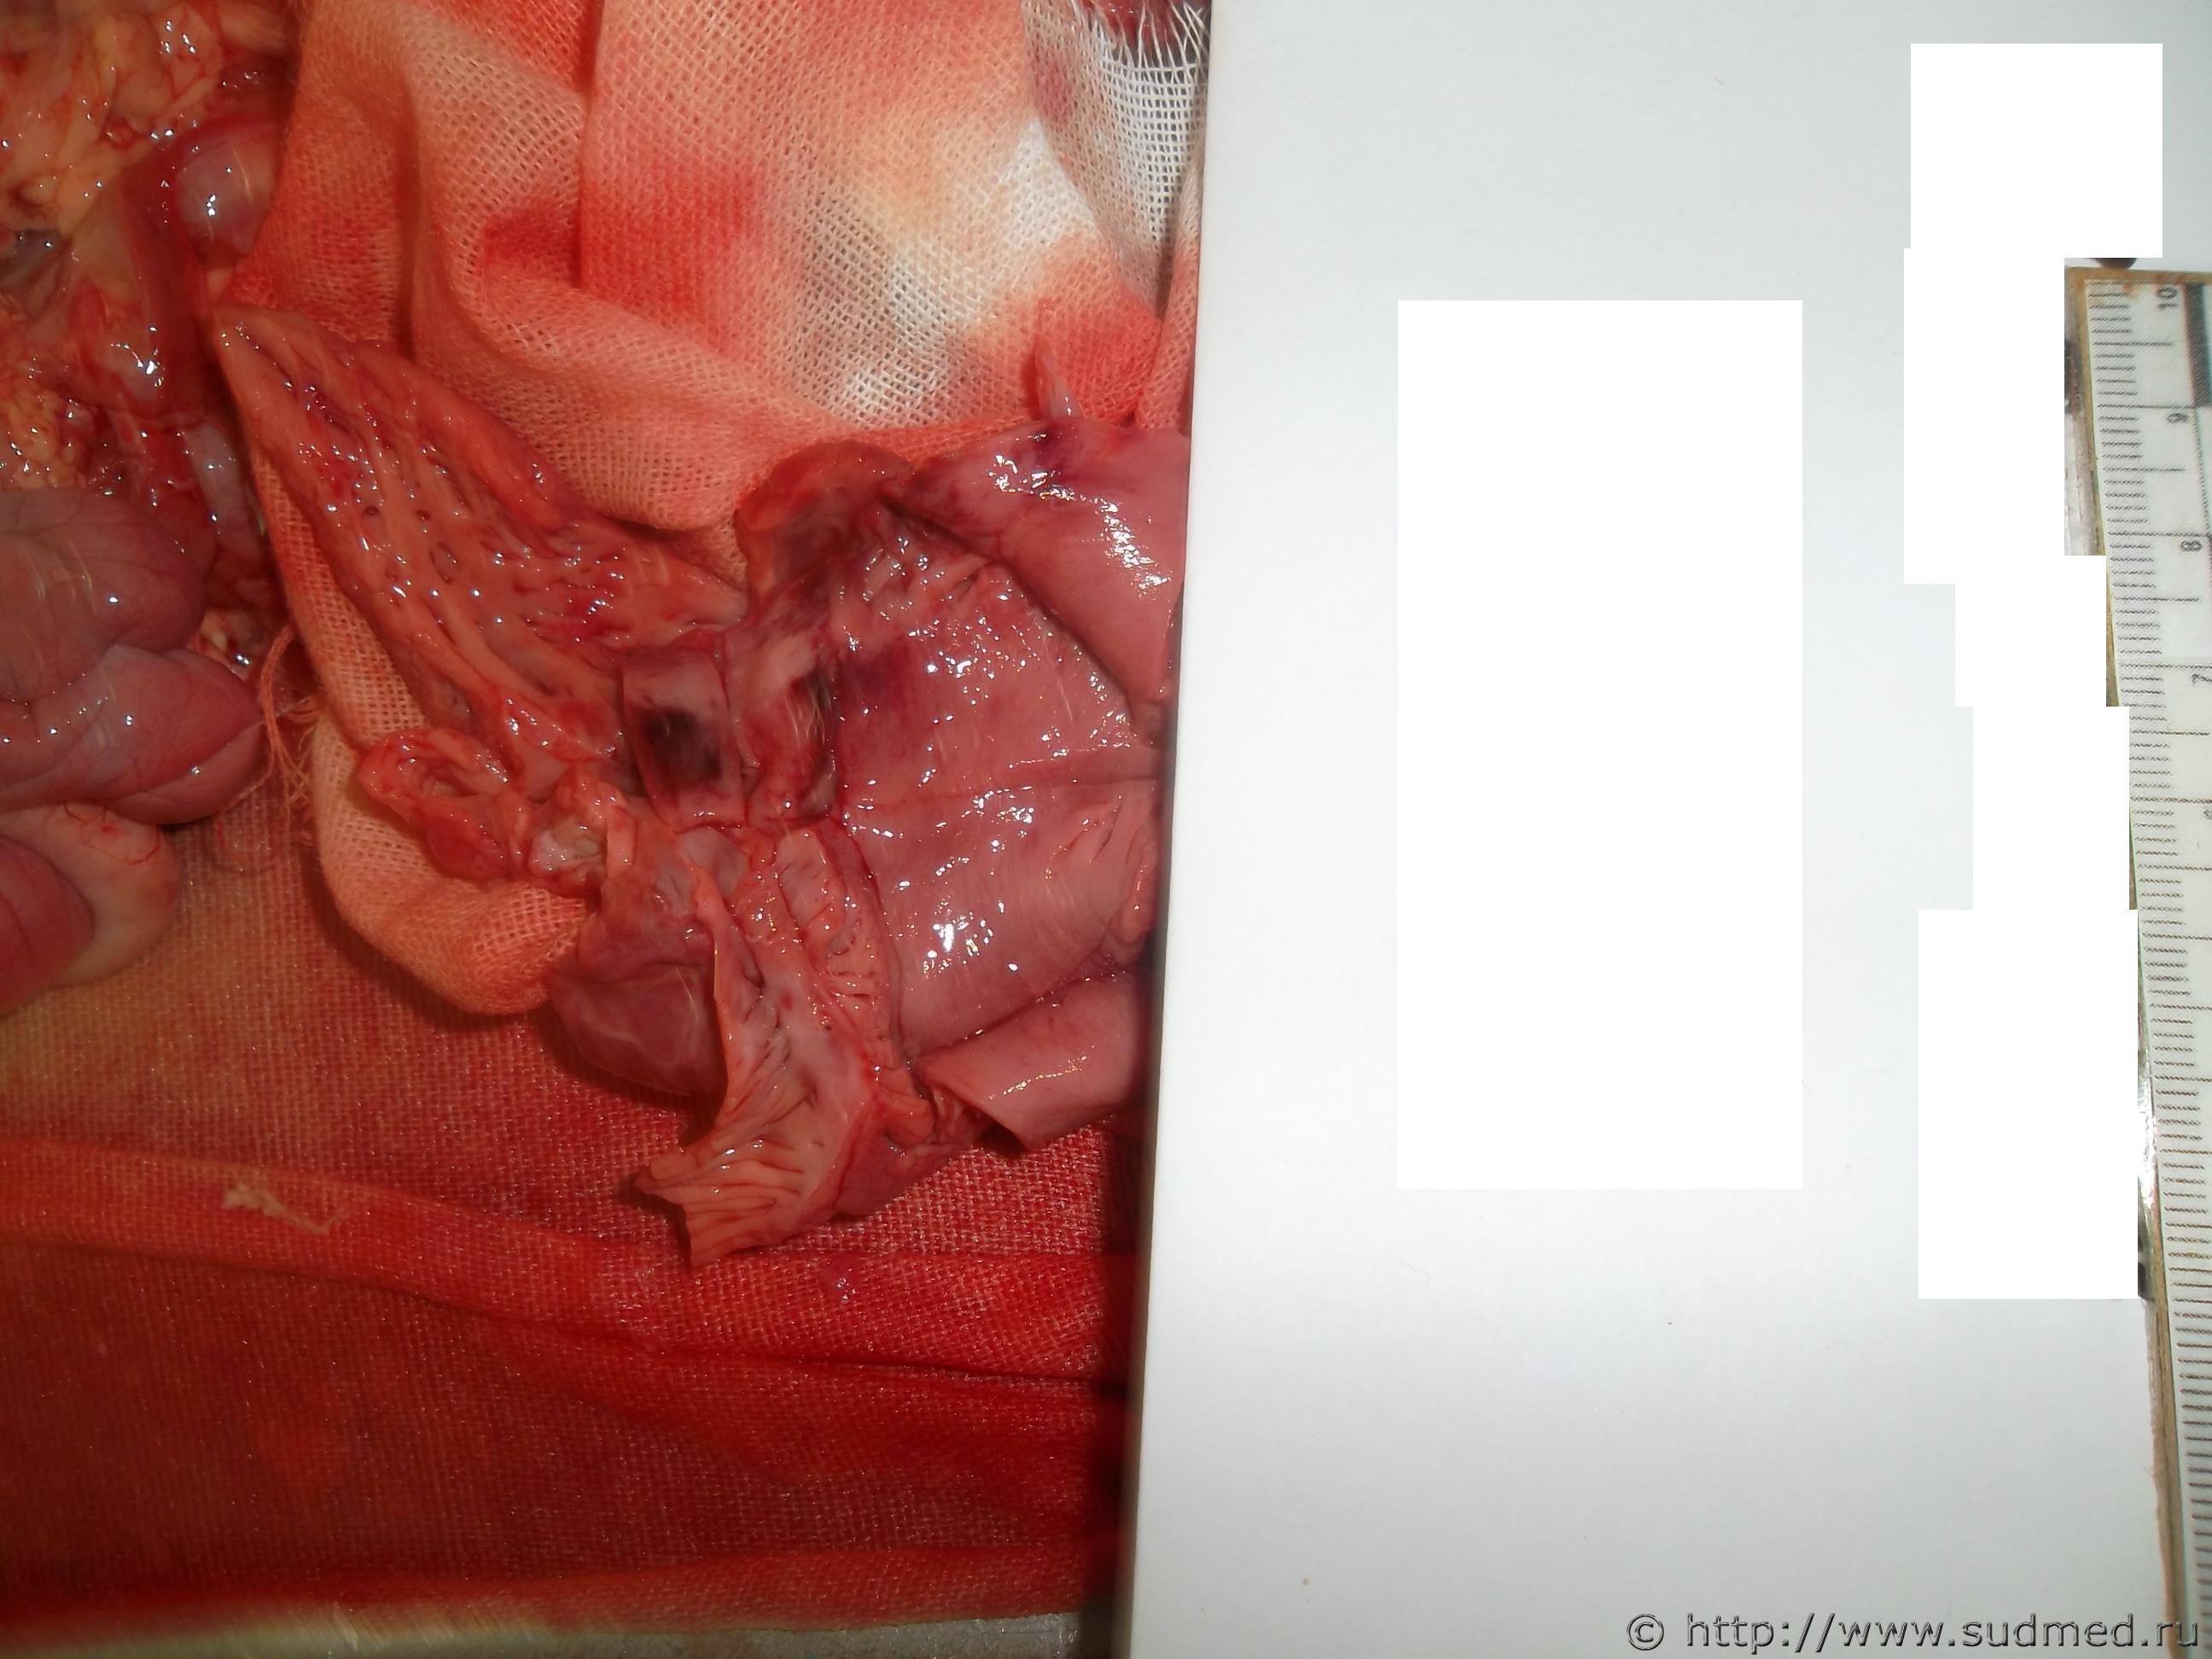

ребенок 5 мес (гистологии пока нет)

Плоховато вижу.Это интрамуральное или же субэндокардиальное кровоизлияние? Вроде вижу и то и другое.Есть ли кровоизлияния в др.органах,слизистых и серозных оболочках? Обстоятельства дела?

А что даст гистология? В данном случае только,то что имеет место инфильтрирующее кровоизлияние?Гляньте на миокард вне кровоизлияний,что там есть за инфаркт?

К сожалению случай не мой, просто не мог пройти мимо - впервые вижу у ребенка. Кровоизлияния есть под плеврой (множественные), из анамнеза - в марте перенесла операцию по лигированию аортального протока; кроме этого при вскрытии обращает на себя внимание только плотноватые включения овальной и округлой формы в ткани легких до 0,5х0,5см (бронхо-легочная дисплазия), ребенок родился массой 820 гр, незаращение овального окна и боталлового протока)

Вот с МВПР надо и начинать,а все кровооизлияния,включая и это - в осложнения,вероятно, здесь ДВС-синдром.

Не каждое кровоизлияние в ткани сердца - инфаркт. Учитывая, что были и субплевральные кровоизлияния, а вероятнее всего и еще где нибудь, то речь идет о проявлении какой либо системной патологии (ДВС к примеру). А вот что к этому привело - надо разбираться. Я последний раз нечто подобное при менингококковой инфекции видел.